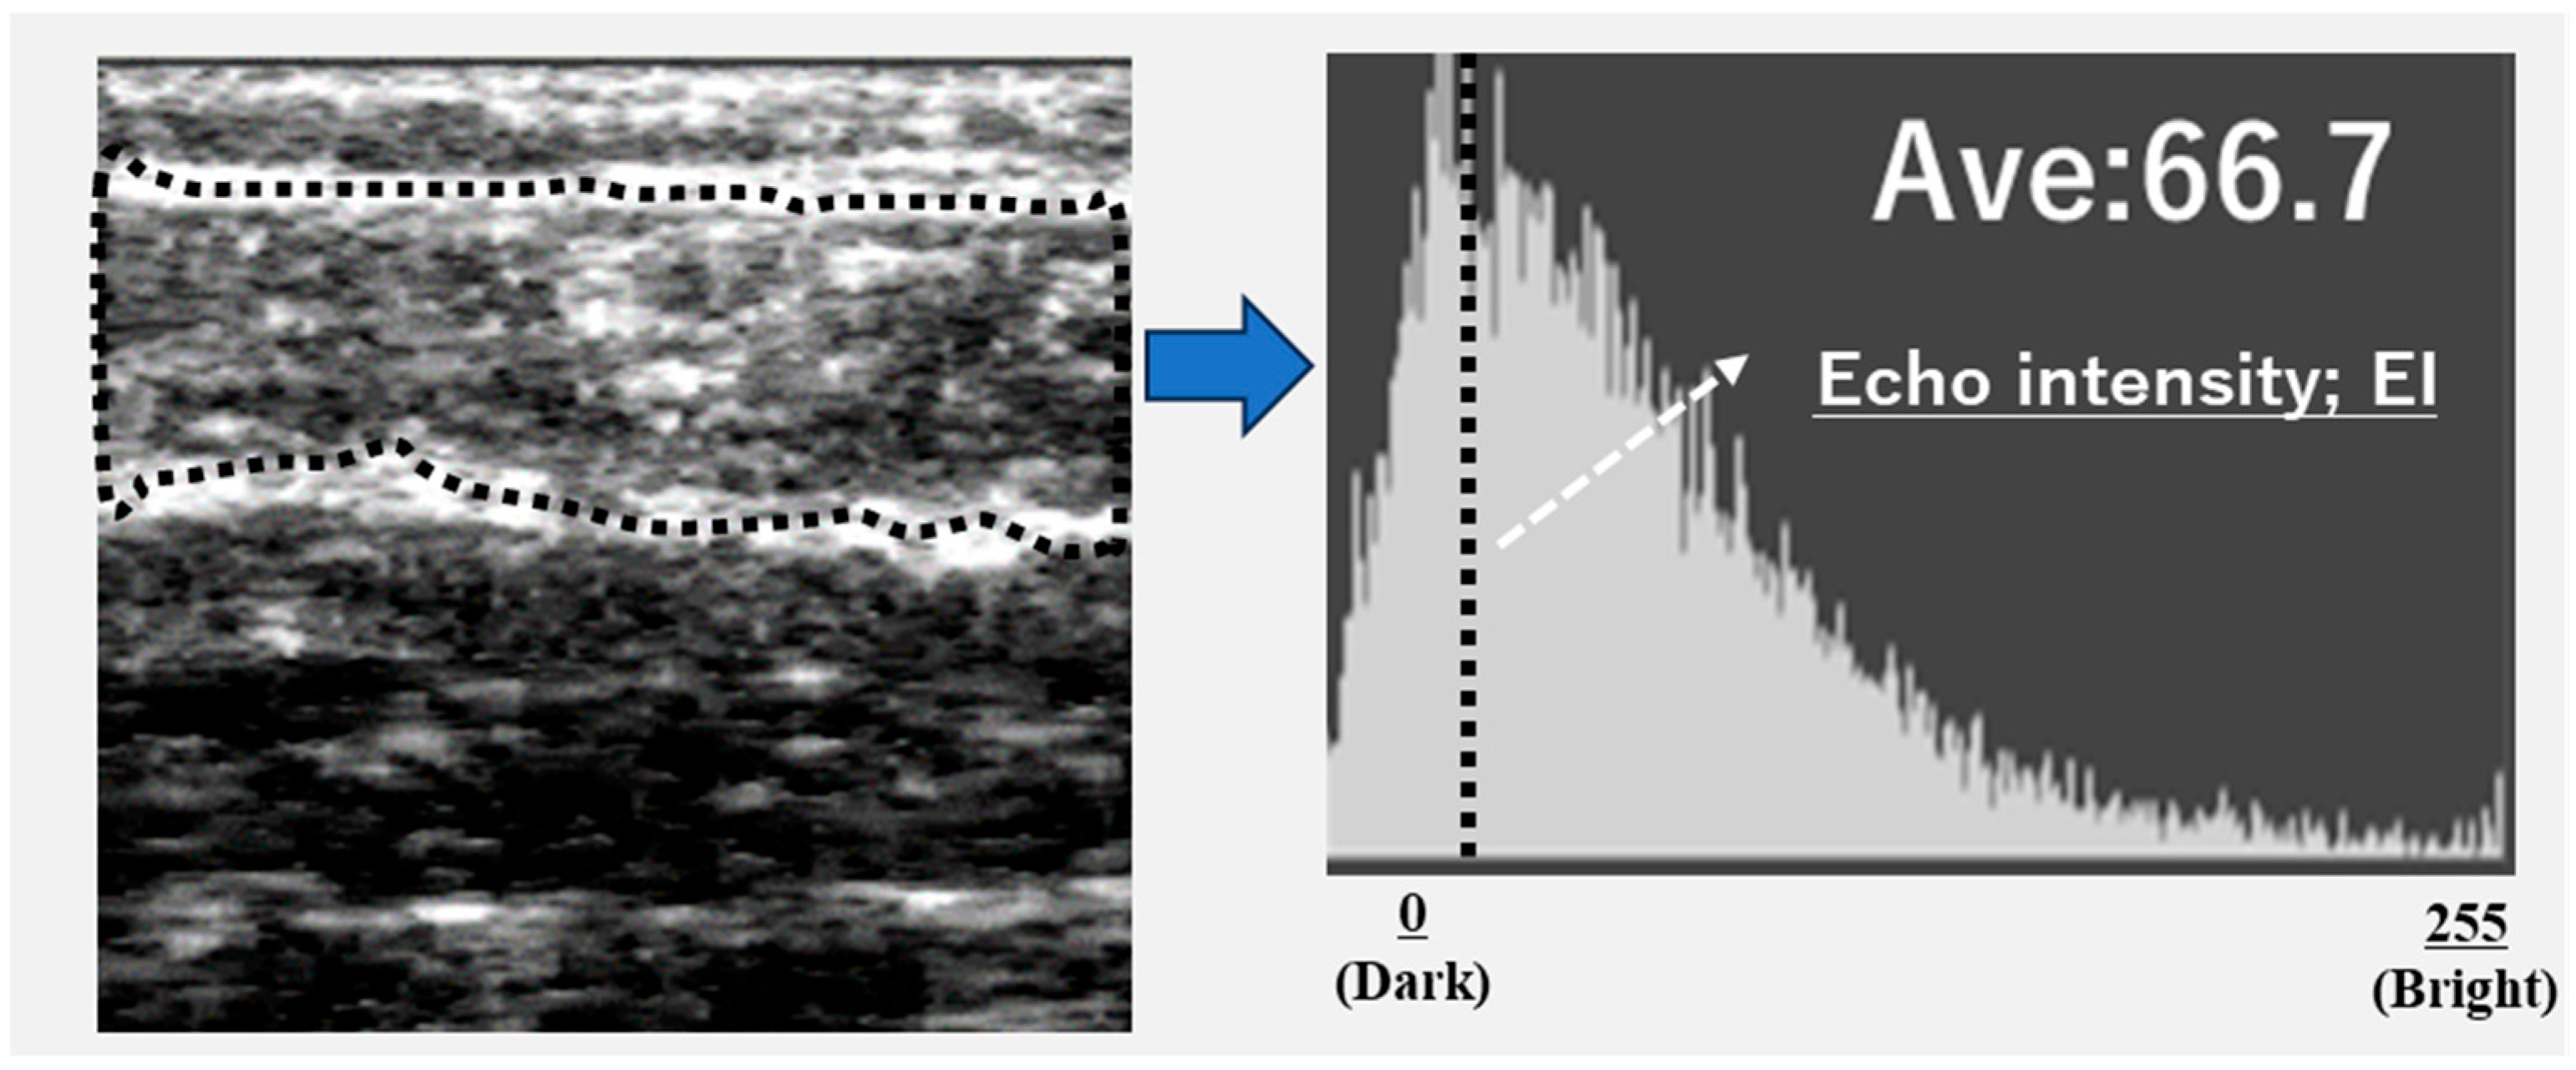

The images of the gastrocnemius muscle were obtained using an ultrasound device (View’s i; SAKAI Medical Science Co., Ltd., Tokyo, Japan) equipped with a 6-MHz linear array probe. In all patients, ultrasonography measurements were performed under fixed settings, including B-mode, a fixed dB dynamic range, fixed gain, and fixed depth of focus, which were preconfigured for skeletal muscle imaging and intentionally made non-modifiable by the manufacturer. The mode settings are not disclosed due to the device’s patent protection. The participants were assessed in a seated position with both knees flexed at 90° and the ankles at 0°. The examiner vertically and gently positioned the probe on the right medial gastrocnemius at the point of maximum below-knee circumference. The A-mode display on the device was monitored simultaneously. The examiner captured images of the subcutaneous adipose tissue and gastrocnemius muscle (Figure 1). The subcutaneous fat thickness (SFT) was defined as the distance between the skin surface and the upper fascia of the gastrocnemius. Meanwhile, the GT was defined as the distance between the subcutaneous fascia and the deep fascia. A previous study investigated the intra-rater reliability of GT measurements in healthy adults when the probe pressure was maintained below 100 gf [9] reported decreased reliability under this condition. Based on these results, we set the probe pressure at 200 gf in this study to minimize measurement error.

Ultrasound images were exported as Joint Photographic Experts Group (JPEG) files, and the EI of the gastrocnemius muscle was calculated using Adobe Photoshop Elements (Adobe Systems, Inc., San Jose, CA, USA). The target area was selected to include as much muscle tissue as possible while avoiding the surrounding fascia. The selected area was converted to an 8-bit grayscale image, with the mean image brightness presented as a value ranging from 0 (black) to 255 (white) (Figure 2). The EI was calculated as the mean image brightness [10]. This study analyzed the EI and GT of the leg with the lower ABI.

Figure 1. Ultrasonographic image of the gastrocnemius muscle; ① subcutaneous fat thickness; ② gastrocnemius thickness (GT).